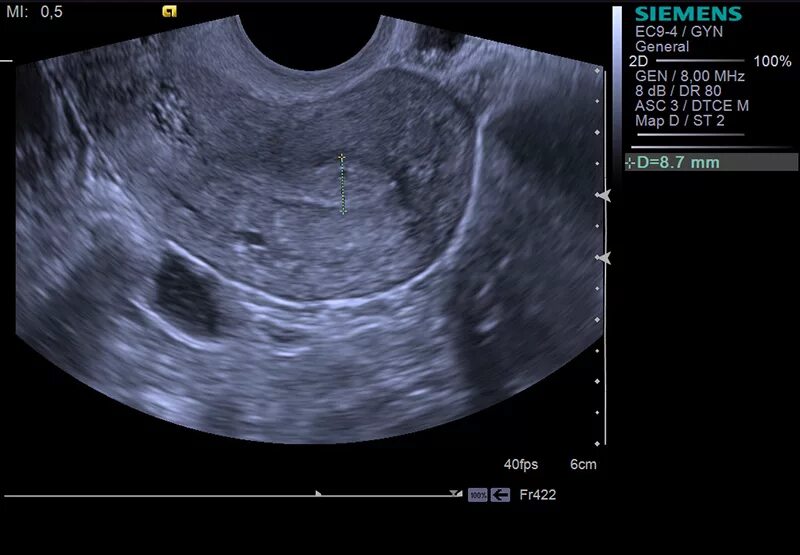

Узи малого таза можно ли при месячных